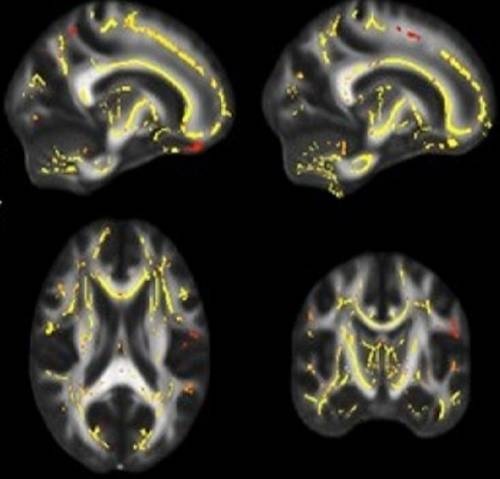

Estas imágenes cerebrales muestran píxeles amarillos y rojizos que representan áreas donde la funcionalidad de la materia blanca está asociada con niveles más altos de aptitud física. Las imágenes están basadas en datos acumulados de pacientes que participaron en el estudio. (Imágenes: UT Southwestern Medical Center)

El equipo de Ding reclutó pacientes de edad avanzada con un alto riesgo de desarrollar el Mal de Alzheimer. Las personas con este nivel de riesgo exhiben los primeros signos de pérdida de memoria, o deterioro cognitivo leve. Los investigadores determinaron que estar en baja forma física se correlacionaba proporcionalmente con una materia blanca más débil, lo que a su vez se correlacionaba con una funcionalidad cerebral inferior.